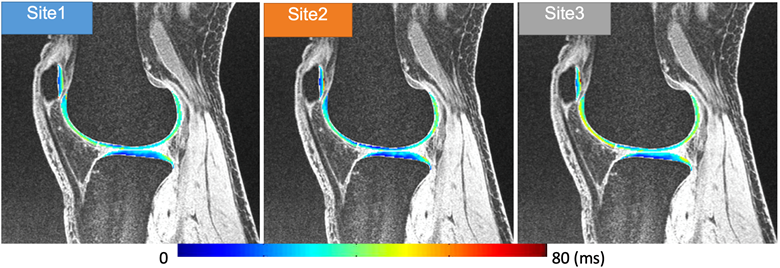

Multi-vendor Multi-site Novel Accelerated MRI Relaxometry

PI: Xiaojuan Li, PhD

Co-Is: Carl Winalski, MD; Kunio Nakamura, PhD; Nancy Obuchowski, MD; Erika Schneider, PhD; Kurt Spindler, MD; Morgan Jones, MD

External Collaborators: Leslie Ying, PhD (New York State Univ. at Buffalo); Peter Hardy, PhD (Univ. of Kentucky); Thomas M. Link, MD; Jing Liu, PhD (UCSF PI); Chris Peng, PhD (Einstein College of Medicine); Kathryn Keenan, PhD (NIST); Elizabeth Mirowski, PhD (Verellium); Ravinder Reddy, PhD (Univ. Penn); Brian Hargreaves, PhD (Stanford Univ)

Funding Sources:Arthritis Foundation; NIH/HIAMS R01 AR077452

MR T1ρ and T2 relaxation times have shown to be promising imaging biomarkers for early cartilage degeneration, and prediction of disease progression. However, many challenges to clinically applying these techniques remain, including lack of standardized acquisition and quantification methods, and long acquisition time. We have implemented MAPSS T1ρ and T2 imaging sequences on three major MR platforms (Siemens, GE and Philips) and have performed multisite multivendor cross validation and reproducibility evaluation, sponsored by the Arthritis Foundation. The next step is to develop fast T1ρ and T2 imaging techniques using novel MRI reconstruction and evaluate the reproducibility and clinical significance of the technique in a multivendor multicenter setting in volunteers and patients with osteoarthritis. A dedicated MSK calibration phantom will be also developed.